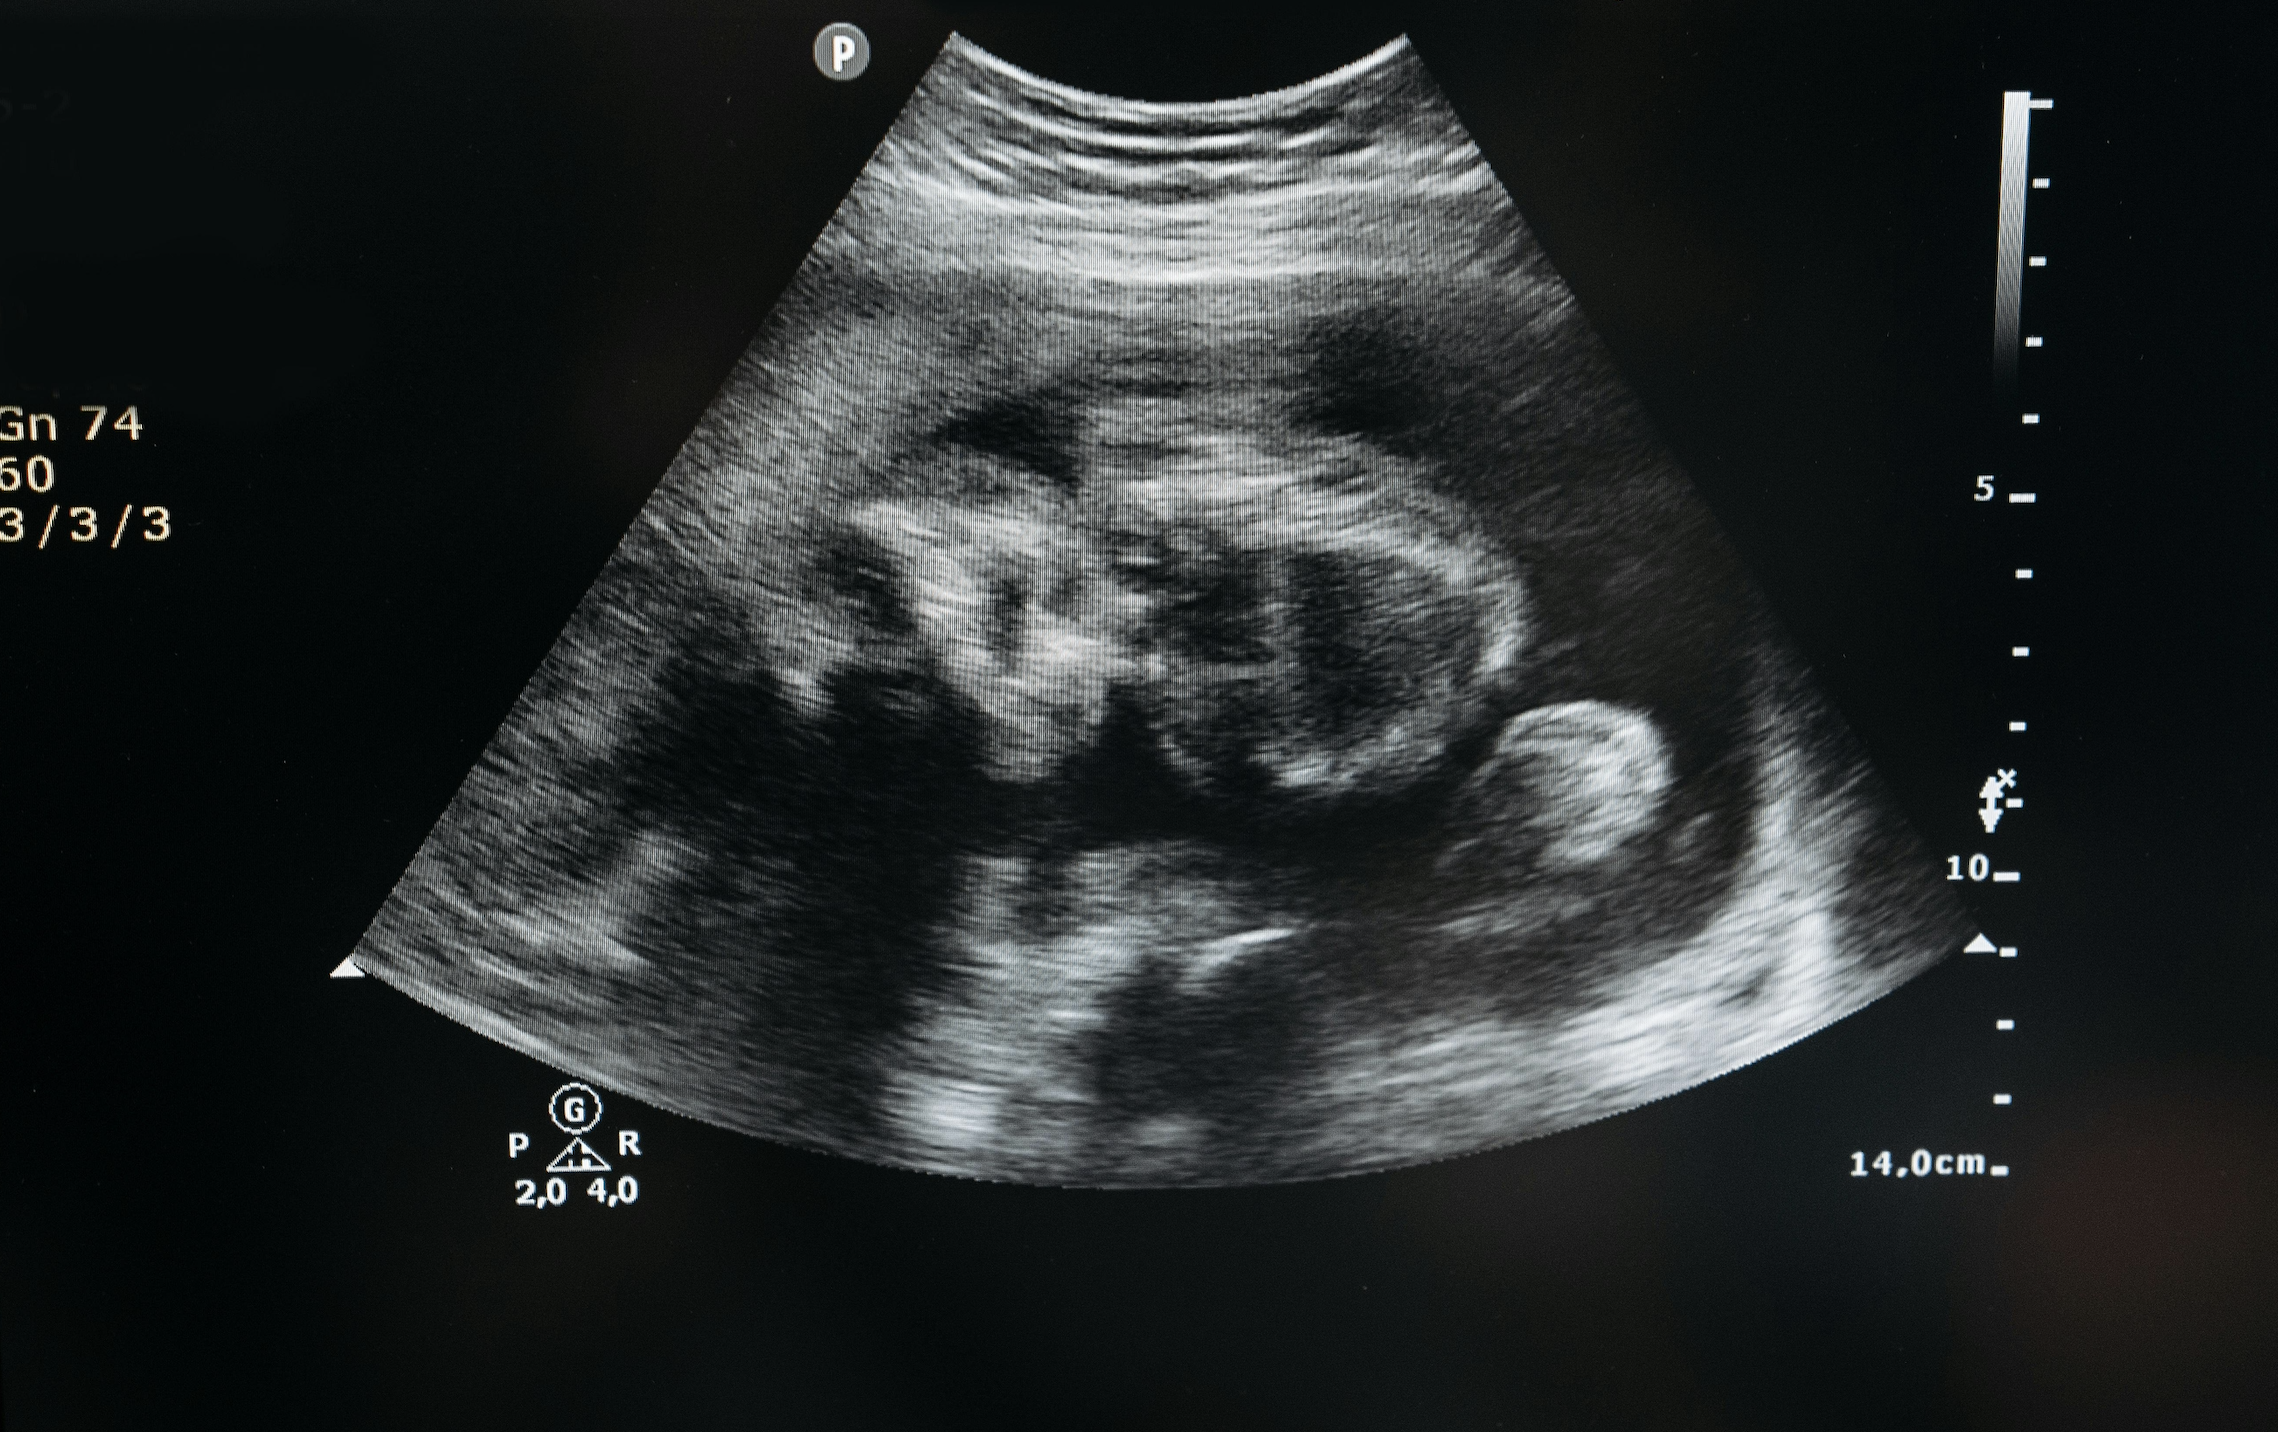

“Shit”, twee streepjes op de test. De zwangerschapstest, achttien jaar en zwanger. Iets wat toch regelmatig voorkomt, omdat je jong en onbezonnen bent. Ook een angst van mij. Ik heb het geluk met een stabiele relatie en een hele lieve vriend, maar toch zou een kindje absoluut nog niet welkom zijn. Voor een abortus kiezen is al een moeilijke keuze en om dan nog eens te bedenken dat vreemde mensen je voor de kliniek willen tegenhouden, omdat het embryo in jouw buik volgens hen recht heeft op leven, is voor mij een feit waar ik niet met mijn hoofd bij kan.

Eén op de vijf vrouwen in Nederland raakt ongepland zwanger in haar leven. Hiervan gebruiken twee van de drie vrouwen anticonceptie. Wanneer er dus verantwoordelijke keuzes worden gemaakt of er wel of geen kinderwens is, is zwanger raken helaas niet uit te sluiten. Er bestaat namelijk geen enkele anticonceptie die voor de volledige 100 procent betrouwbaar is. Hoewel veel mogelijkheden in de buurt komen, is er te allen tijde bij vruchtbare vrouwen een kans op een ongeplande zwangerschap.